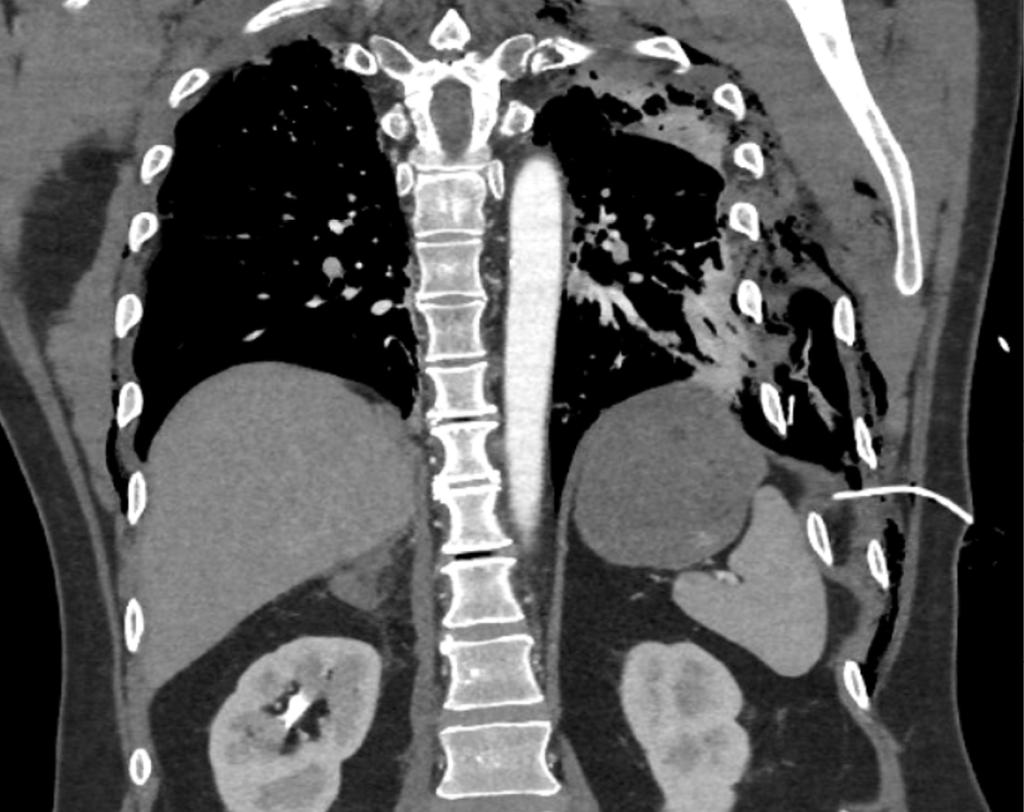

Bij aankomst van het Mobiel Medisch Team (MMT) wordt de patiënt beademd met masker en ballon vanwege het feit dat de ademfrequentie progressief is gedaald. Vanwege het vermoeden van een ernstig neurotrauma wordt de patiënt door het MMT gesedeerd, geïntubeerd en beademd. Echo-onderzoek van de borstkas laat beiderzijds longsliding zien, wat suggereert dat er op die plek geen sprake is van pneumothorax. De patiënt wordt zonder verdere interventies naar het ziekenhuis vervoerd. Daar laat een CT-scan van de thorax zien dat de patiënt beiderzijds meerdere ribfracturen en subcutaan emfyseem heeft. Er zijn kleine ventrale pneumothoraxen zichtbaar. Aan de linkerzijde zijn de ribfracturen sterk verplaatst en is er sprake van longcontusie. Hoewel de patiënt positieve-drukbeademing krijgt, zijn er geen aanwijzingen voor een spanningspneumothorax. Ook is te zien dat de thoracocentesekatheter onder het diafragma eindigt, en niet in de pleuraholte (figuur 1).

Figuur 1

Locatie thoracocenthesekatheter bij patiënt A

Figuur 1 | Locatie thoracocenthesekatheter bij patiënt A

‘Curved multiplanar’ reconstructie van een CT-scan van de thorax van een patiënt van middelbare leeftijd na een verkeersongeval. Er zijn beiderzijds meerdere ribfracturen zichtbaar en subcutaan emfyseem. Aan de linkerzijde zijn de ribfacturen sterk verplaatst en is er sprake van longcontusie. Er zijn kleine ventrale pneumothoraxen aanwezig, maar geen aanwijzingen voor een spanningspneumothorax. In de linker flank is een thoracocenthesekatheter ingebracht; deze eindigt onder het diafragma.